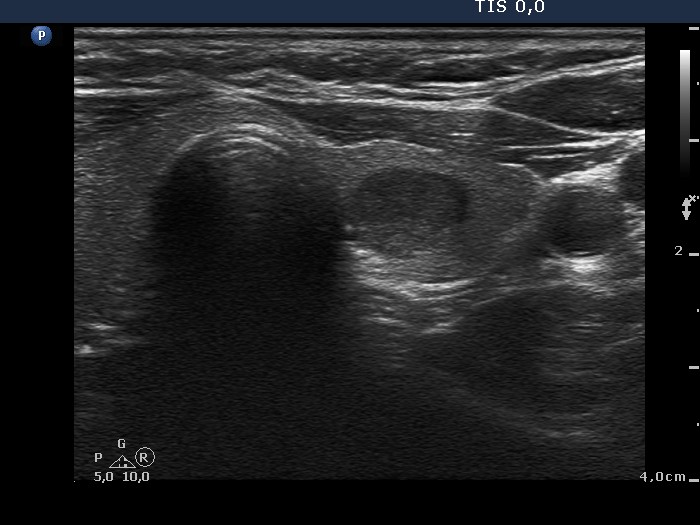

Ultrasonography. The thyroid was minimally hypoechogenic. The left lobe contained a cystic lesion that was completely or almost completely cystic. The lobe had two hypoechogenic nodules next to each other, which presented microcalcifications and irregularly increased intranodular vascularization.

A total thyroidectomy was performed. Histopathology disclosed Hashimoto's thyroiditis. The cystic lesion proved to be a hyperplastic nodule while corresponding to the nodules in the lower part of the left lobe, oxyphilic variant of papillary carcinoma was diagnosed.

It was doubtful whether the cystic lesion was true nodule or a normal finding, a dilated marcofollicle. The histopathologist did not find any lesion corresponding to the cystic lesion, so it was only a cystic area and not a pathological nodule.